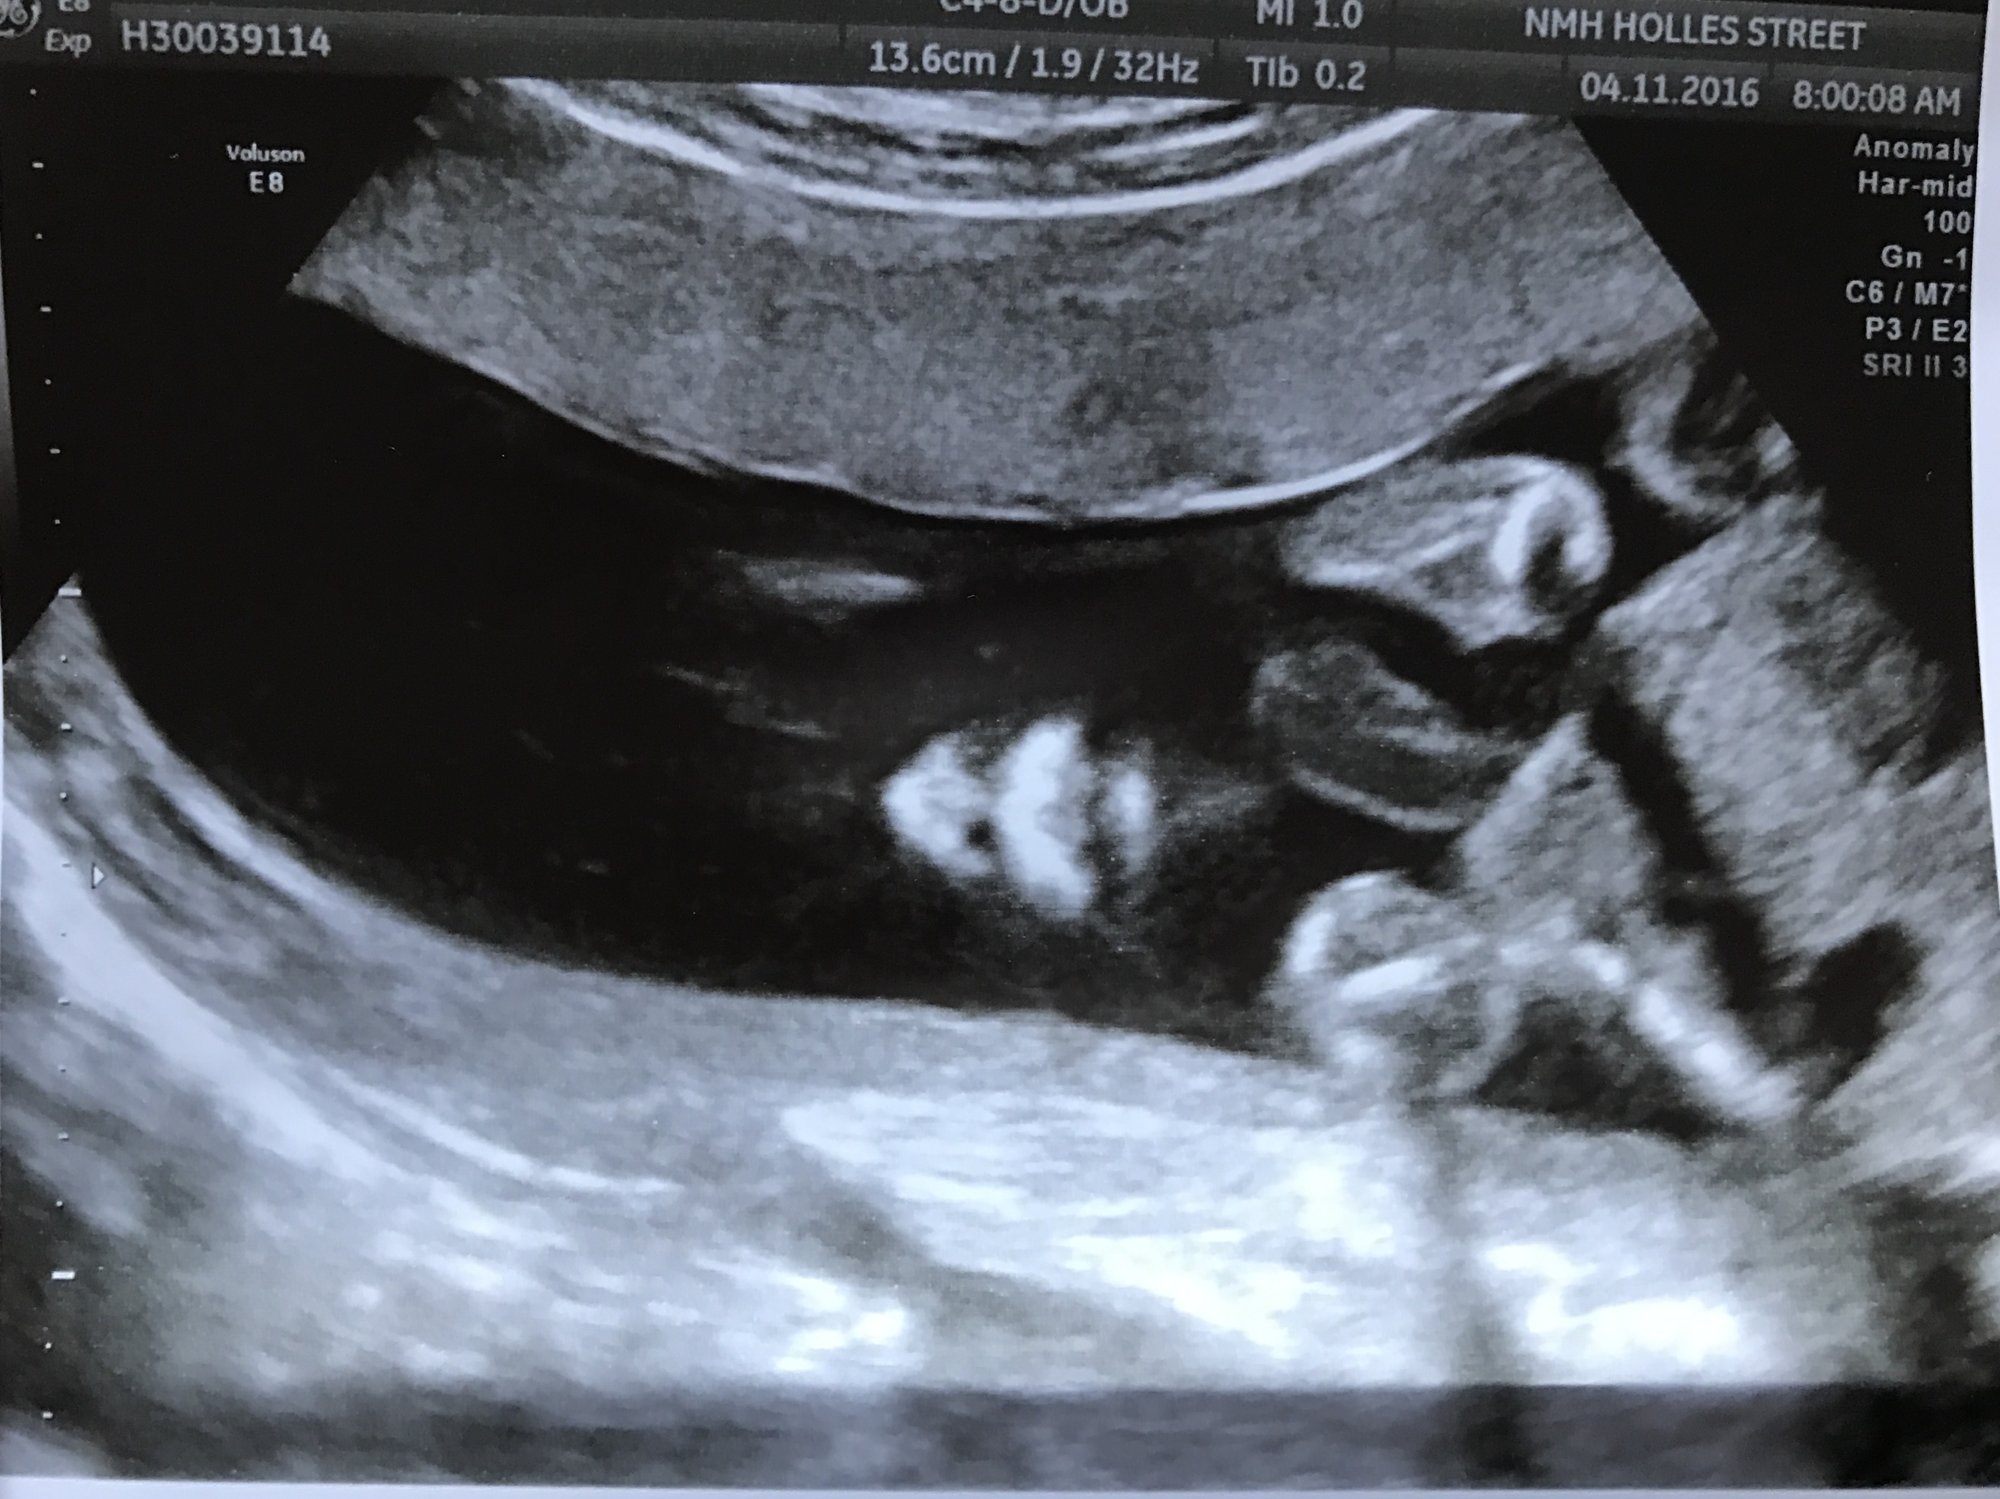

This little stinker didn't want to cooperate for her anatomy scan this morning - she wouldn't sit still! And just when our tech was starting to get frustrated she stopped, smiled, and waved hello. And my whole heart melted into a puddle on the floor.